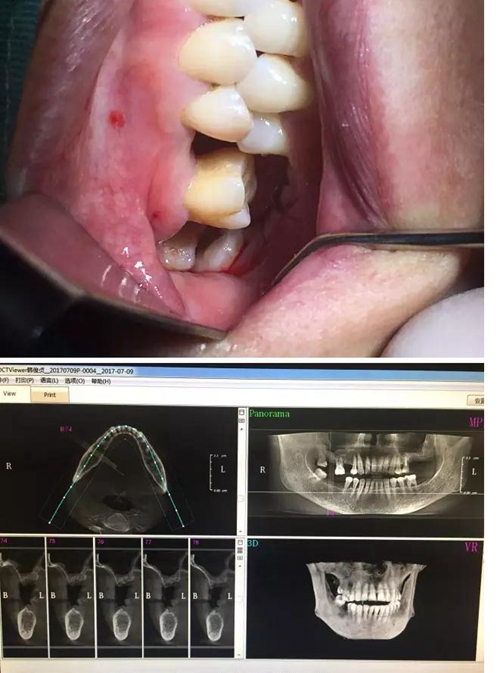

【病例分享】內(nèi)提,用自體骨柱,不用骨粉

1.jpg